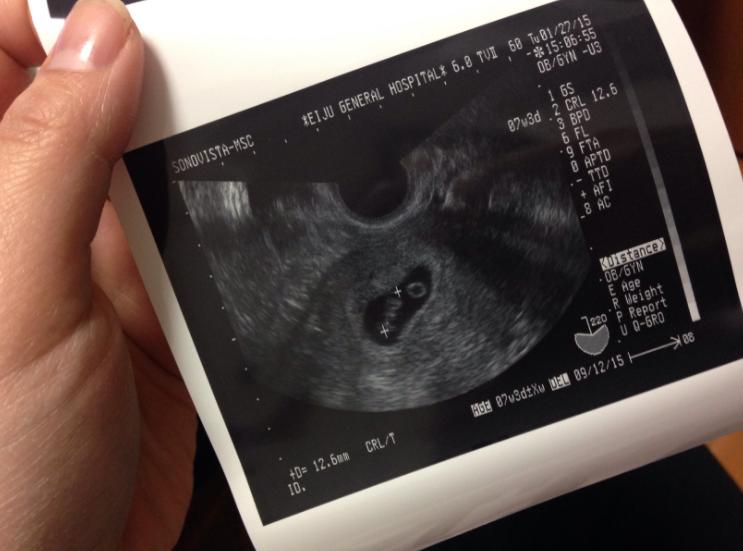

可能过几天后发现“又来了月经”,也可以叫“孕期出血”,细心的女性可能还会发现:上厕所时看到“有一个较大的血块掉了下来”,然后急急忙忙去医院检查,医生安排做了B超,单根本看不到“胚胎”,这种情况就叫“生化妊娠”。

一般生化妊娠发生在怀孕5周内,也就是在查出怀孕后不久,有“出血”现象,然后小的小胚胎就随着出血溜掉了。